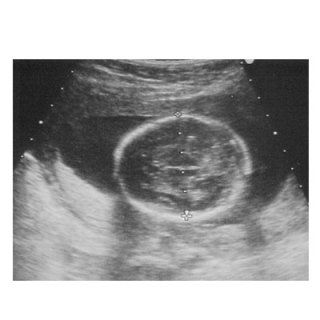

Lo Studio Radiologico e di Diagnostica per Immagini del Dott. Gianfranco Famiglietti, esegue valutazioni della biometria fetale e lo studio funzionale del feto.

Inoltre esegue indagini ecotomografiche encefaliche sia fetali che neonatali.